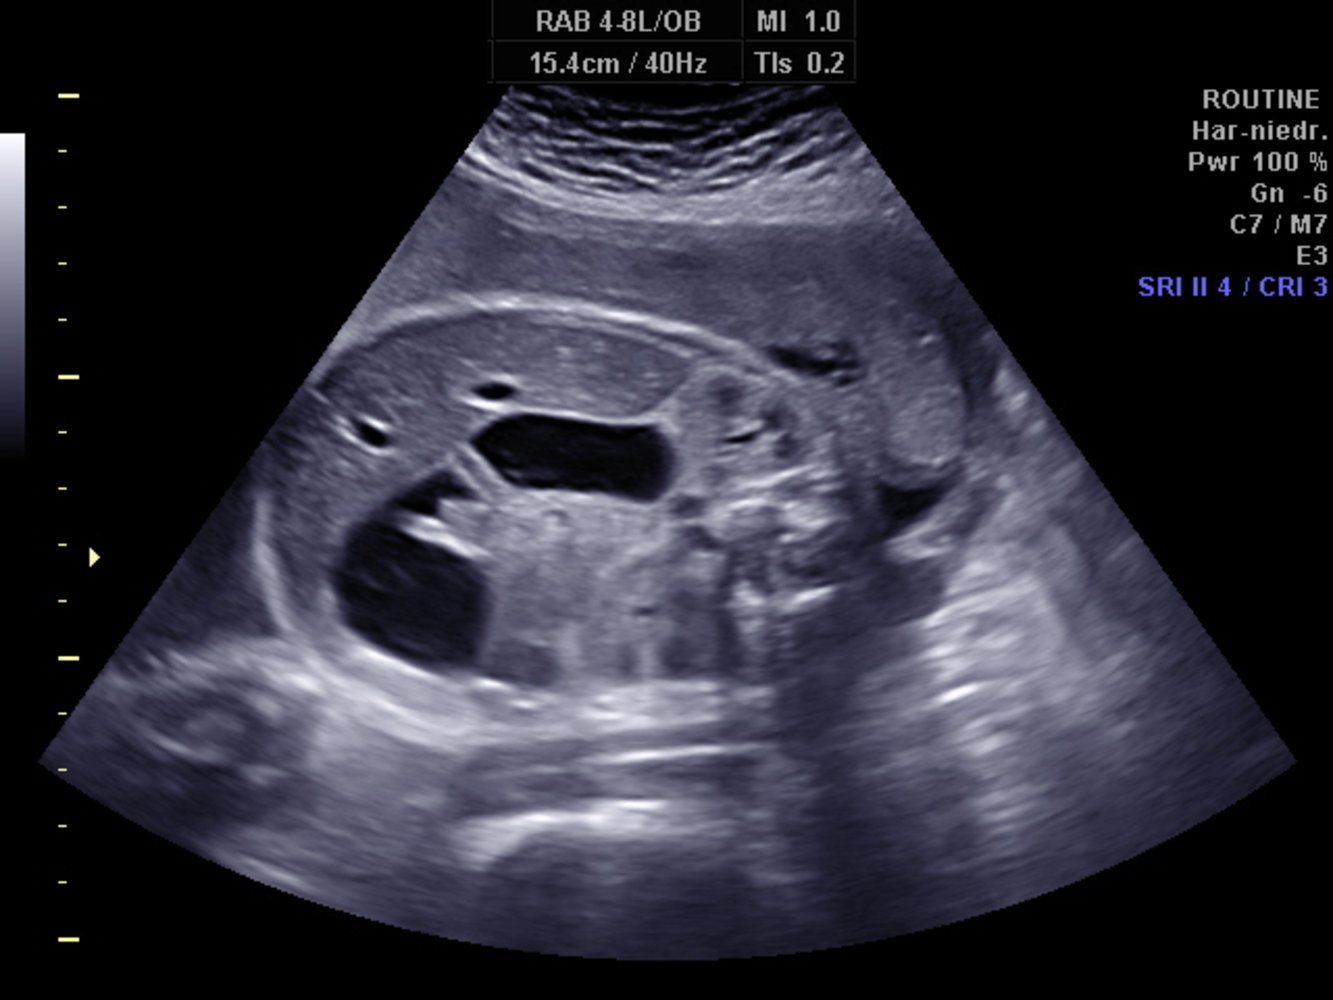

Double Bubble Sign on Ultrasound Seen in Duodenal Atresia

S → stomach

D → proximal duodenum

Shaded area → pyloric sphincter

(dilation of the pre-stenotic bowel segments (duodenum (D) and stomach (S)) with an air-fluid level in each dilated segment (double bubble sign). No air is visible in the post-stenotic bowel loops)